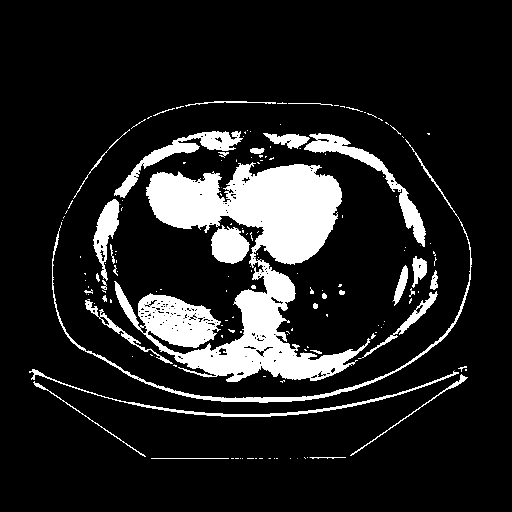

Image Grid

4Γ—3 grid: Rows show different image types (Original NATIVE, Reconstructed NATIVE, Original VENOUS, Generated VENOUS), Columns show windowing techniques (No Window, Lung Window, Mediastinum Window)

Original VENOUS CT scan

Full window (WL 1023.5, WW 4095 β†’ Low βˆ’1024, High +3071)

Actual HU range: [-1024.0, 3071.0]

Lung window (WL -600, WW 1500 β†’ Low βˆ’1350, High +150)

Actual HU range: [-1350.0, 150.0]

Mediastinum window (WL 40, WW 400 β†’ Low βˆ’160, High +240)

Actual HU range: [-160.0, 240.0]